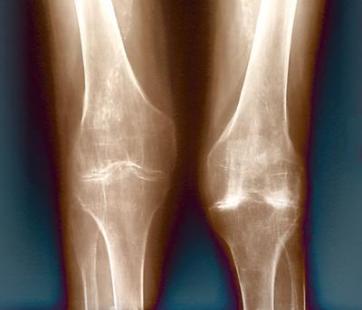

Une prescription de tramadol a été faite chez M. A, 50 ans, opéré d'une prothèse de genou pour réduire les douleurs post-opératoires. Vu la persistance de ces dernières, le traitement a été renouvelé à plusieurs reprises par différents médecins et se disant insuffisamment soulagé, M. A a augmenté la dose journalière à 300/400 mg par jour. Il se plaint d'effets secondaires à type de somnolence et de constipation. Néanmoins, toutes ses tentatives d'arrêt du tramadol se sont soldées par des symptômes de sevrage avec sueurs et angoisses qui l'ont amené à reprendre le traitement. Il souhaiterait pouvoir arrêter le traitement mais craint « de ne pouvoir s'en passer ». Pour son médecin traitant, il s'agit avant tout d'évaluer la dépendance physique et psychique de son patient vis-à-vis de l'opioïde.

Première étape, le médecin doit réévaluer la douleur. Le maintien et l'augmentation des doses de l'antalgique peuvent être liés à la persistance de la douleur : dans le cas de M. A, une consultation auprès de son chirurgien peut vérifier l'absence de problème à ce niveau. Il faut aussi bien analyser ce qui revient au nociceptif et ce qui relève du neuropathique dans la douleur, afin d'éventuellement rectifier le traitement.